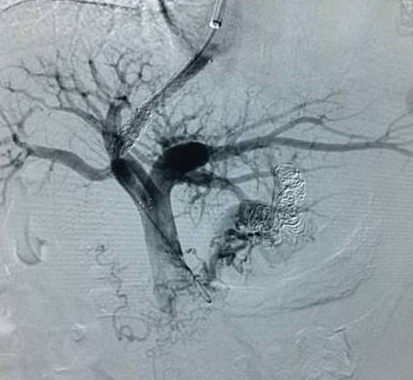

高飞教授与我科王立非主任联合完成了这例手术。TIPS之所以是“高大上”的介入手术,是因为医生手术时虽然只面对一个平面的屏幕,但要在肝内的肝静脉穿刺门静脉,必须要有全面的空间立体感,还要选好支架通道的路径。随着置入肝内支架的打开,门静脉血流瞬间被分流至腔静脉,一条“生命通道”搭建完成,患者门脉压力由术前38mmHg降至术后26mmHg。术后仅是在患者右侧颈部留下5mm大小穿刺口1个,术后患者无再出现呕血,术后7天复查CT显示术前明显迂曲增粗的食管胃底静脉已消失;现患者已康复出院。